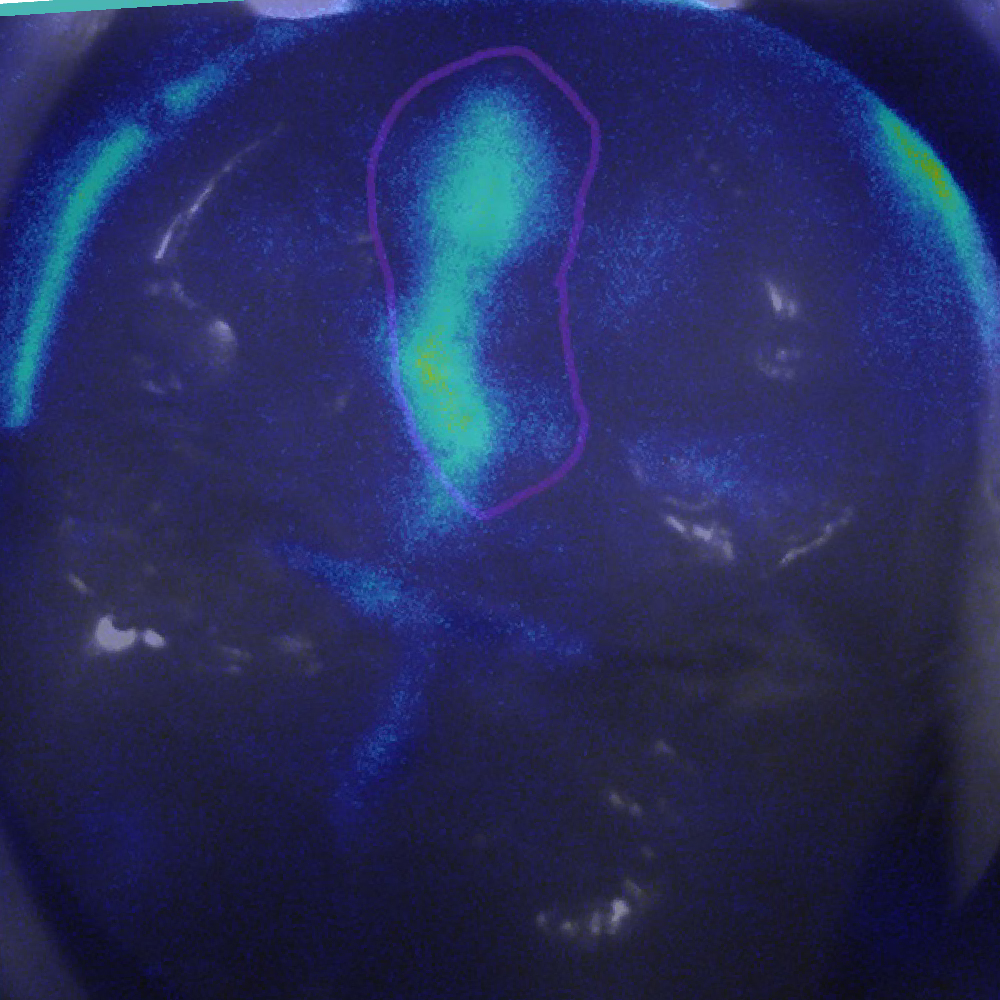

IMAGE 2

Can you differentiate?

0

SOUND

Quiz Image Overlay Overlay

Prevention/Treatment Pathway Options

Low Caries Risk – Baseline Prevention

Medium to High Risk – Fissure sealant

Supported by:

• Fluoride for prevention (all teeth)

• OHI/Education

• Regular screening with Calcivis Imaging

This tooth has a developmental anomaly and is hypoplastic; therefore, applying a fissure sealant could be an option to remove plaque retention sites and thus reduce the patient’s caries risk.